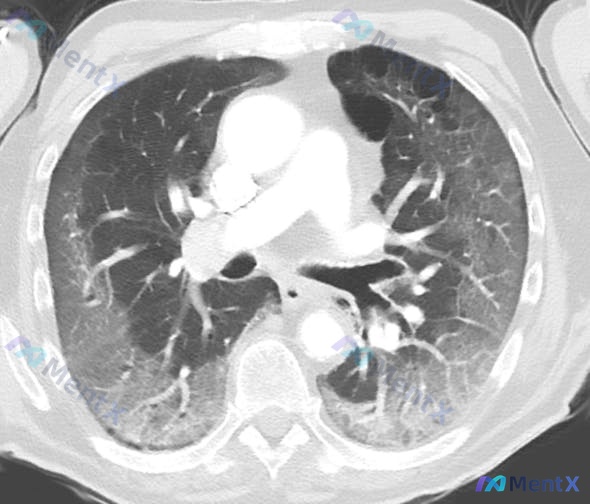

整理到一个病例,先抛出来大家一起看: 56岁女性,6天来低烧、关节肌肉痛、呼吸急促逐渐加重,症状前先有嗅味觉减退。病史有肥胖、高血压,用赖诺普利。同事很多有类似症状,丈夫昨天也开始不舒服。 生命体征:体温100.9°F,血压114/72mmHg,脉搏94次/分,呼吸20次/分,BMI 33.5kg/...

整理了一份经典的呼吸道感染病例,先把前期资料放出来: 61岁男性,因鼻窦充血、呼吸困难、疲劳和咳嗽就诊,三周前从中国武汉旅行返回,两个月前接种过年度流感疫苗,发病前身体状况良好。 生命体征:心率92次/分,呼吸频率20次/分,体温38.2°C,血压100/60 mmHg。 辅助检查:胸部X光显示双侧...